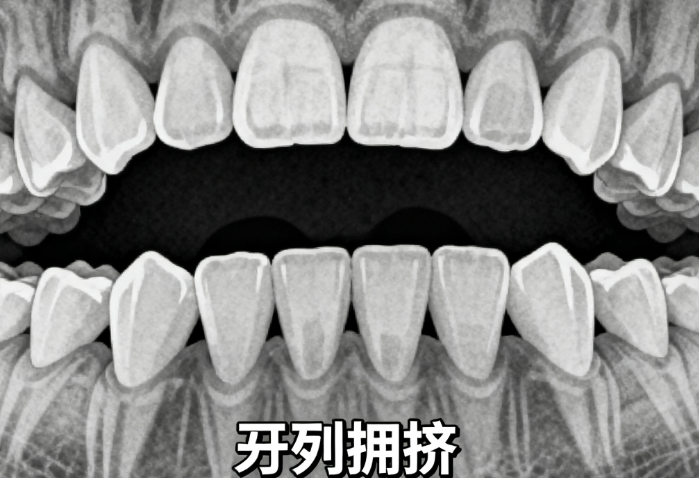

在当下口腔健康与面部美学日益受到重视的背景下,牙齿矫正逐渐成为大众关注的医疗需求。作为豫东地区的重要城市,商丘汇聚了多家在正畸领域具有影响力的医疗机构。如何选择一家技术可靠、服务优质的矫正医院,既关乎治疗疗效,也影响着后续的健康管理。本文将从医疗技术、设备配置、医生团队、服务体验等维度,为读者系统解析商丘地区矫正牙齿的优选方案。